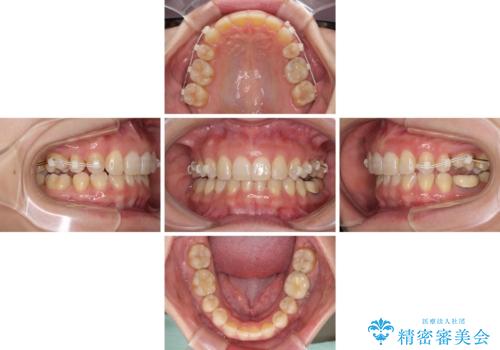

下顎2前歯の欠損 インビザラインによる抜歯矯正

いずれもワイヤー矯正が望ましい治療方法ですが、家が遠方であり、近い将来出産される予定もあるとのことで、何とかマウスピース矯正でも対応可能な③にて治療を行うこととしました。

マウスピースでの抜歯矯正特有の抜歯スペースに向かって奥歯が傾斜する動きが顕著に表れ、ディープバイトは改善されませんでした。

前歯のみが強く接触し、奥歯で咬めない期間も続いたため、ワイヤー装置などを補助的に使用し、何とか終了させることができました。